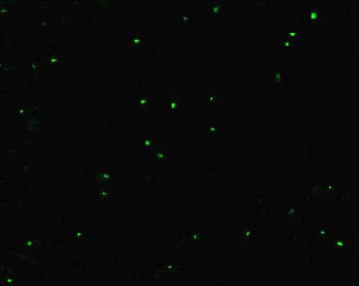

Correlation of Plaque Titers to Epifluorescence Counting

Counting by epifluorescence microscopy using oligreen ssDNA quantitation reagent (Molecular probes Inc., USA) provided an independent, fast, efficient and inexpensive alternative to the transmission electron microscope method and also resulted in more precise and accurate estimates of virus (11-13).

Virus containing samples at various dilutions were stained with Oligreen ssDNA quantitation reagent (2 mg/ml in tris EDTA [TE] buffer pH 7.5) for at least 20 min at room temperature in a foil wrapped container. A 10 ml aliquot of the suspension was spotted onto a clean glass slide and 22mm2 cover glass (Fischer 11/2 ) was placed on the top. The slides were viewed with Zeiss LSM 510 confocal microscope under excitation/Emission at 500/520nm by using a 63X objective. Viruses were found to adsorb approximately equally to both the cover glass and the slide, and the value obtained was multiplied by 2 to account for the surface not counted in any one field (13). Commercially available FluoSpheresR - carboxylate modified microspheres, 1.0 mm diameter blue fluorescent (Molecular Probes, USA) were used as an additional guide to calibrate our epifluorescence counting. An aliquot containing 100 microspheres diluted from 3.6 x 1010 microspheres/ml stock solution was spotted on the slide and counted by epifluorescence.

M13 virus provides a convenient, abundant and safe model pathogen for our ultrasensitive molecular zipper assay and is a filamentous bacteriophage which infects E. coli. We prepared a bulk culture of E. coli and M13 by established techniques (9) employing polyethylene glycol (PEG) precipitation and centrifugation to obtain a yield of ~ 1014 viruses/ml. Plaque assays on lawn of E. coli were initially used to determine the M13 titers. However it was necessary to quantify the phage stock by an independent method to investigate if the M13 purification procedures might have rendered some of the viruses non-infective by damage or loss of tail fibers. This is important because if the damage was significant, the plaque assays could artificially over estimate the real assay sensitivity at the ultrasensitive range of 1-100 virus particles if a substantial portion of the M13 is functionally defective in plaque formation, but yet could contribute to signal in the molecular zipper assay. Therefore, the plaque assay titre was correlated using the epifluorescence counting of M13 for correction of M13 titers. Oligreen ssDNA reagent (Molecular Probes, USA) stains only the single strand DNA (figure 1a) allowing the measurement of the fluorescent counts and provide a second method to estimate virus titers for correction of estimation obtained with plaque assay.

Figure 1: a Epifluorescence microscope study of M13 stained with Oligreen ssDNA quantitation reagent. Various dilutions of the virus stock were stained with Oligreen ssDNA quantitation reagent for 20 min and a 10 μl aliquot was spotted on the cover slip.

b Epifluorescence microscope results of E. coli JM109 stained with oligreen ssDNA quantitation reagent as a negative control.

In our results the discrepancy was ~17.6% (Table 1) with more viruses seen by epifluorescence at low levels of the analyte indicating some loss of infectivity by the purification procedure.

Table 1: Estimation of M13 concentration using epifluorescence counts.

We observed an error percent of 2.4 in our epifluorescent count estimation using FluoSpheresR - carboxylate modified 1.0 mm diameter blue fluorescent microspheres. E. Coli when used as a negative control is not stained by oligreen (figure 1b) but can be visualized with propidium iodide, acridine orange or gold nucleic acid stain that binds double stranded DNA (data omitted) . This result indicated that the Oligreen ssDNA reagent was specifically detecting M13 and not contaminating bacteria or their components.